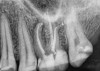

Excellent diagnosis essentially begins with two fundamental components: a doctor willing to listen to the patient’s chief complaint, and proper diagnostic tools. Among the most important tools are a precise periapical radiograph (PA) and bitewing (BW). Although a PA is often enough to provide an accurate portrayal of the patient’s condition, sometimes it alone does not suffice. Figure 1, Figure 2, and Figure 3 demonstrate a case that illustrates this point clearly. Despite two acceptable PAs (Figure 1 and Figure 2), it is difficult to assess the source of the patient’s pain to temperature. However, the BW radiograph Figure 3 provides significantly more clarity than either of the two PAs. The BW depicts localized bone loss (around tooth No. 2), a pulp stone (No. 2), a flat occlusion, numerous calcified canals, multiple restorations in tooth No. 30, and gross decay especially on tooth No. 3, which is the source of the patient’s pain to temperature. In this instance these images depict how much more useful a BW can be than just a conventional PA.

Fig 1. Foreshortened PA radiograph.

Figure 1